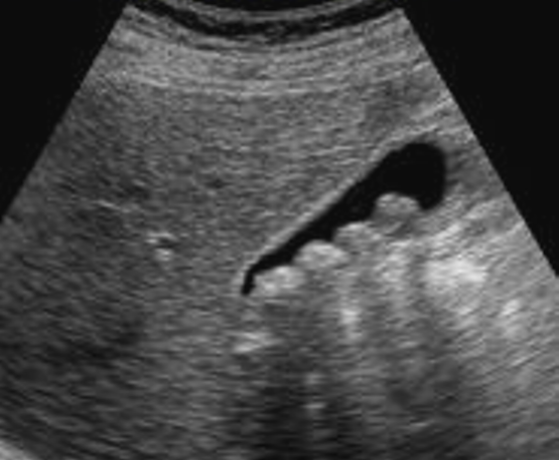

Las neoplasias de la vesícula biliar son una patología poco frecuente, pero es común que lo presenten los pacientes con alguna enfermedad autoinmune, este articulo se trata del reporte de un caso clínico de una paciente de 23 años con el diagnostico de Leiomioma. Los leiomas son tumoraciones benignas de